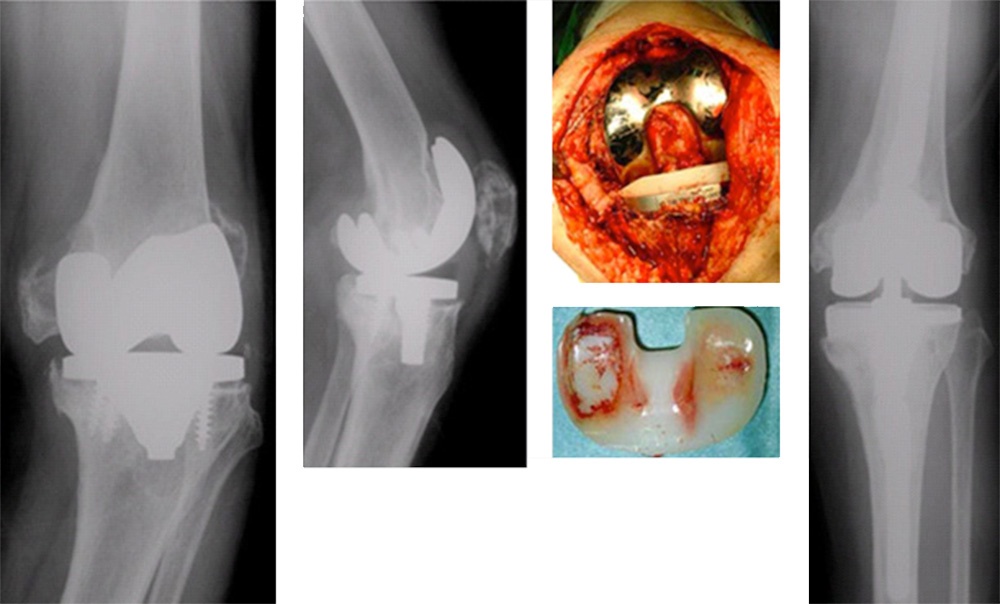

内側型変形性関節症に対して片側型人工関節(UKA)を施行。

人工膝関節全置換術(TKA)

軟骨が徐々にすり減り、最後には軟骨が消失し、骨と骨が擦れあうようになった状態を末期の変形性膝関節症といいます。末期の状態では人工関節以外に有効な治療法がないのが現状です。

高度の内反変形に対して人工膝関節全置換術(TKA)施行。